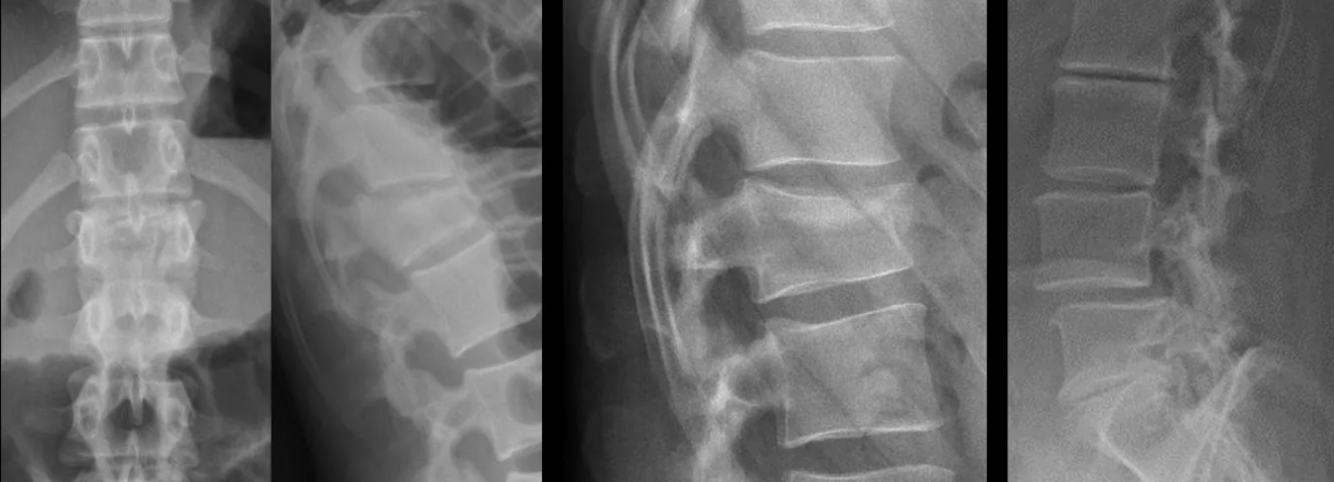

What are the pathologies in this picture?

What are the pathologies present in this picture?